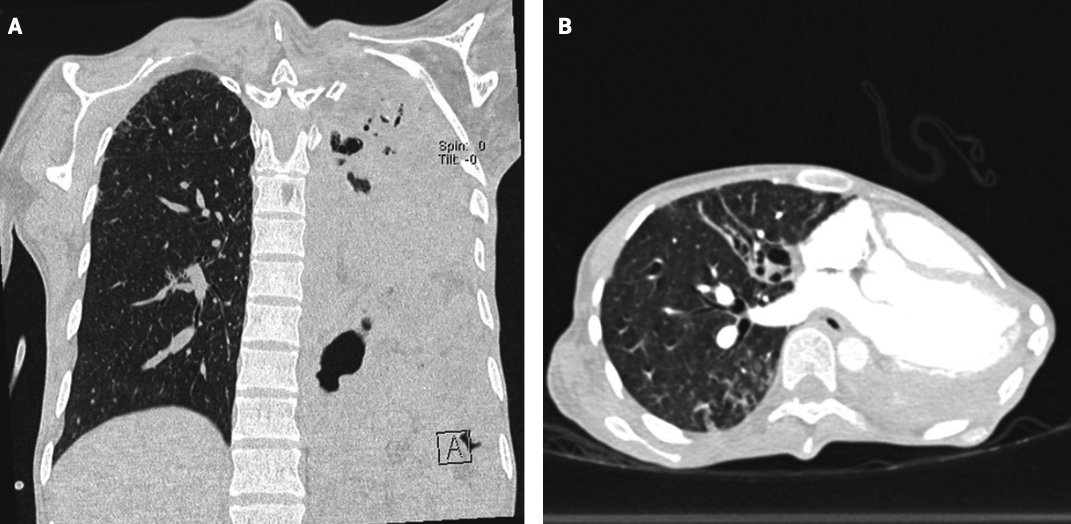

Se determinó la necesidad de atención médica multidisciplinaria, en coordinación con los servicios de neumología, genética, reumatología, cirugía plástica, nutrición clínica, oftalmología y epidemiología. La hipertensión arterial pulmonar se excluyó con base en el ecocardiograma, radiografía de tórax y angiotomografía torácica. En esos estudios se identificaron hallazgos compatibles con tromboembolia pulmonar, evidenciada por el defecto de llenado central en el tronco del lóbulo basal derecho (Figura 2). La anticoagulación se inició con 1 mg/kg de enoxaparina.

<strong>Figura 2</strong>

Figura 2. Radiografía de tórax al ingreso. Hiperclaridad en la región pulmonar basal derecha y discreta disminución de la trama vascular, hallazgos compatibles con alteraciones en la perfusión sugerentes de evento tromboembólico. Pulmón izquierdo con destrucción heterogénea del parénquima y cambios fibróticos, quizá secundarios a daño estructural crónico.

Además, se consideró la posibilidad de tuberculosis pulmonar, debido a la coexistencia de bulla en el segmento apical y múltiples nódulos con tendencia a la confluencia en relación con zonas de consolidación (Figura 3), que se descartó con la baciloscopia negativa.

<strong>Figura 3</strong>

Figura 3. Angiotomografía de tórax con contraste. A. Corte coronal que muestra un defecto de llenado en la rama basal derecha de la arteria pulmonar, compatible con tromboembolia pulmonar aguda. B. Reconstrucción en ventana del parénquima que evidencia la destrucción pulmonar heterogénea, con áreas bullosas y distorsión, con nódulos confluentes, sugerentes de daño crónico.